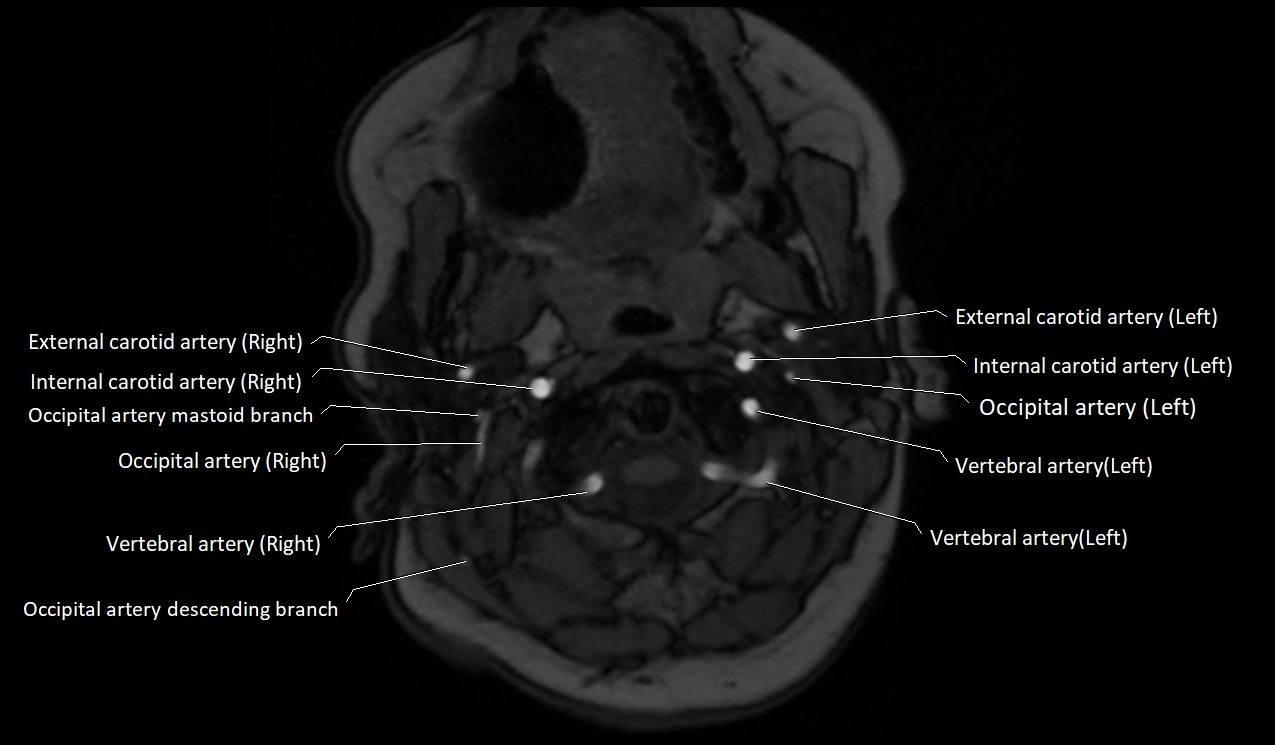

MRI images

image